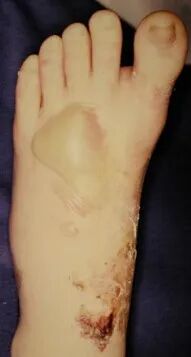

如果不能在伤后6-8小时手术,应耐心等待,待患足肿胀消退出现褶皱时再行手术治疗。若冒然进行手术,可能会加重术后肿胀,或者皮肤不愈合以及皮瓣因压力过大而坏死。

并发症:创伤性关节炎、骨筋膜室综合症、感染、血管神经损伤、内固定失败、疼痛。